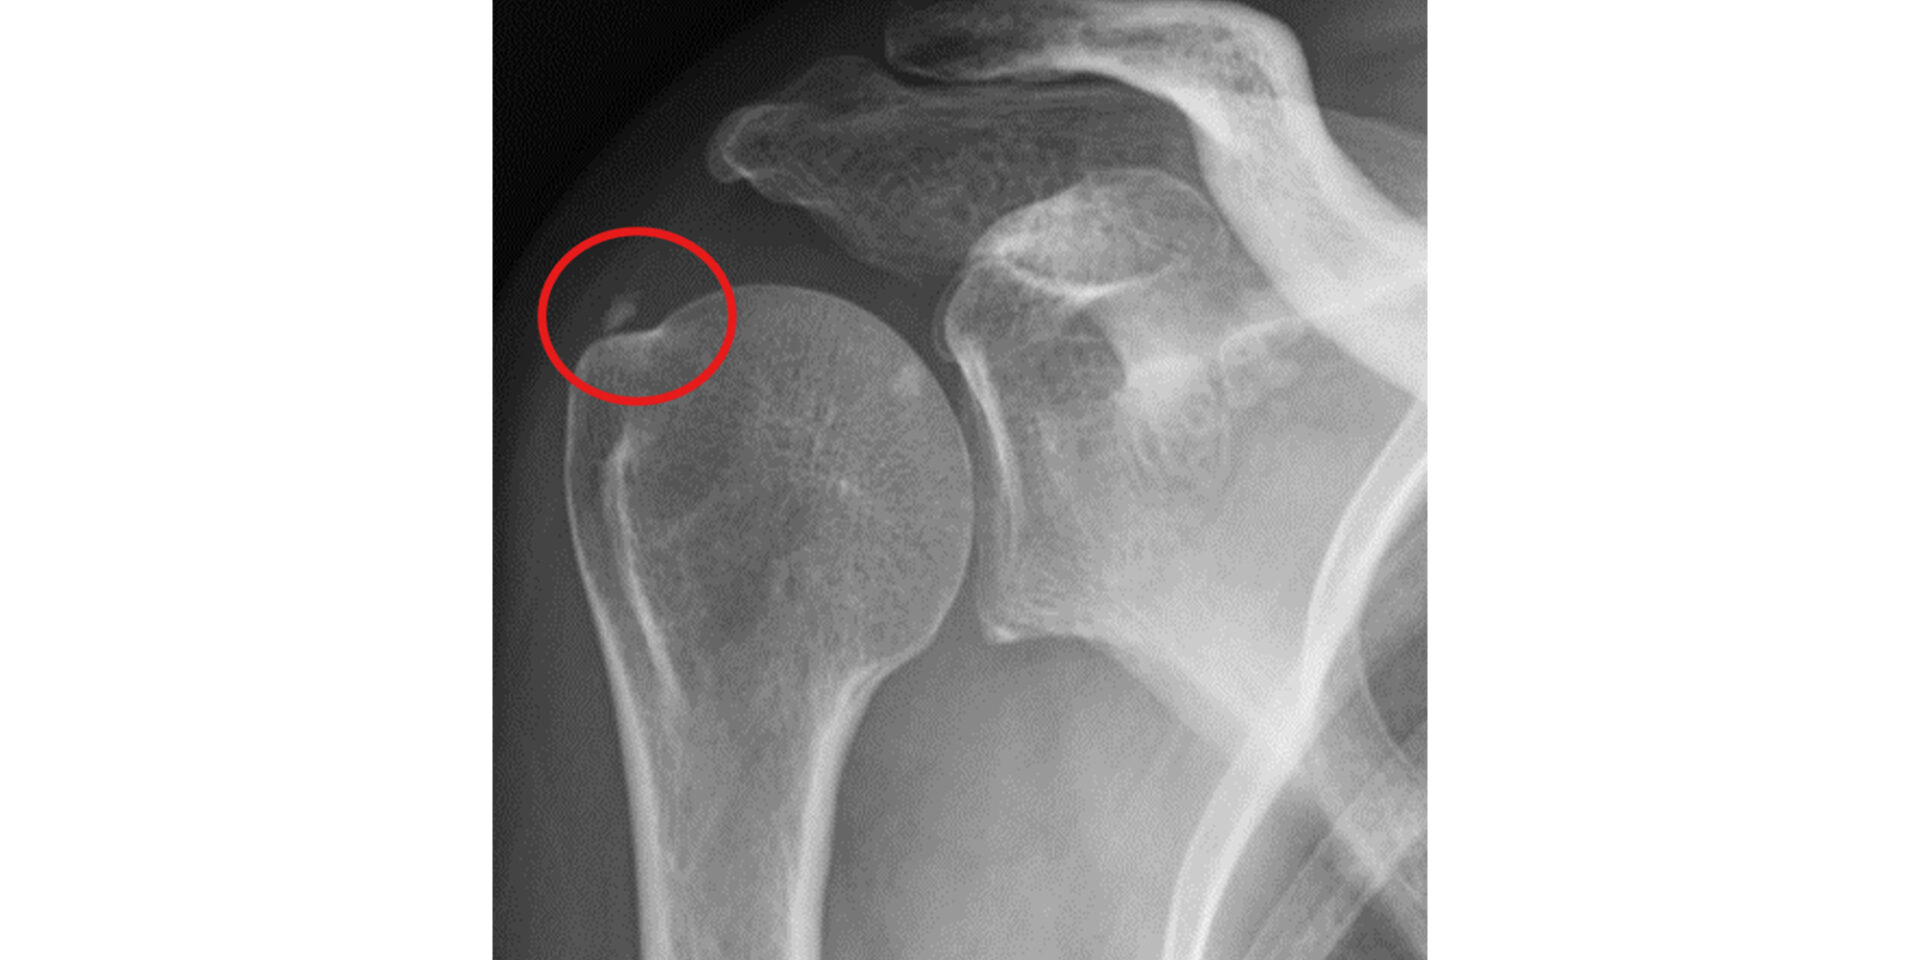

レントゲン(X線)

骨の変形・骨棘(こつきょく)の有無や、石灰沈着性腱板炎の石灰化を確認するために行います。

ただし、腱板は軟部組織のためレントゲンには映らず、腱板断裂の正確な評価にはより詳細な検査が必要です。 -